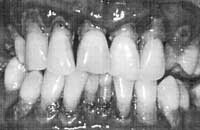

Most of us relate the health of our teeth solely to the presence or absence of dental cavities. A common question that a patient often asks the dentist is — “Are my teeth free from cavities?”  While the absence of cavities is an important indicator of dental health, no less important is the condition of soft tissue, i.e. gums surrounding them.

However, gum health is often ignored. Why? Firstly, because the visible part of the teeth is its white hard part, and that contributes to the looks of the individual; at a younger age, one is naturally concerned more with aesthetics. Secondly, the beginning of gum disease is painless, and its progression too is very slow. Thirdly, at the initial stages of gum disease, there are practically no warning signs. Thus, periodontal (gum) disease develops unnoticed.

Gum disease is directly correlated with oral hygiene. When one ignores regular cleaning of teeth for one reason or another, gum disease sets in. It results from the presence of bacteria called dental plaque near the gums. Insufficient cleaning — or lack of cleaning — results in the piling up of these bacteria in large numbers. This piling up leads to depletion of oxygen supply to the deeper layers of the plaque: an ideal environment for the growth of the harmful anaerobic bacteria which, as its name implies, can live without oxygen.

The toxins produced by these bacteria damage collagen, the main binding structure of the gums. The gums become slightly puffy, while the gingival sulcus deepens and fills with bacteria. As there is no pain at this stage, the disease gets ignored. It progresses slowly, and manifests itself later as unprovoked bleeding from the gums, or bleeding during brushing noticed as pink to red colour in the spit. This is often accompanied by enlarged/puffy gums and foul smell from the mouth.

Gradually, as the disease progresses, it affects the underlying bone, which recedes in order to preserve the remaining healthy structure beneath it. This is precisely what gum or the periodontal disease is. It can be of two kinds: initially it is gingivitis — when the gum around the tooth is involved, and periodontitis when the disease has extended deeper into the bone. Both of these are chronic, i.e., long-standing diseases. With further progression of the disease, and bone destruction, the teeth lose hold of the bone, start migrating and develop spacing. A single tooth may show change in its normal position because of advanced gum disease.

Gum disease begins due to poor oral hygiene. Thus, it is directly related to brushing and flossing.

Any part of the tooth or surface that is not brushed effectively starts developing gum disease. However, brushing with the toothbrush alone is not enough. Dentists have observed that even the most diligent users of the toothbrush develop gum disease between the contacting surfaces of the teeth, also known as proximal surfaces, even though their gums on the other sides (facial and lingual) are relatively healthy. This is because the tooth brush cleans only the front and back surfaces of the teeth. It cannot reach the sides, which can be cleaned only with inter-dental brushes and dental floss.

An alarming fact about gum disease is that the damage it causes is largely irreversible. The bone around the tooth, once destroyed, is gone forever.

If one takes care of oral hygiene using toothbrush, dental floss and inter-dental brush effectively and right from the beginning, one can expect to be free from periodontal disease.  Initially, at a younger age, the inter-dental spaces are tight, and dental floss is recommended. Later in life, as inter-dental spaces become wider, inter-dental brushes can also be used along with dental floss. It must be kept in mind that without the use of dental floss and inter-dental brushes, one would sooner or later develop gum disease.

If one has developed gum disease, with gum treatment procedures like scaling, curettage, gingivectomy, flap operation and bone grafting, depending upon the severity of the disease and its progression can help restore the gum to a disease- free state. What is important is that one maintains good oral hygiene by tooth brushing, flossing and the use of interdental brushing to reduce the risk of getting gum disease. It is also recommended that one regularly examines the oral cavity to see for any changes in the colour of the gums and for swelling and pink stain in the spit as they are the warning signs of gum disease. Also one must visit a dentist every six months to keep one’s 32 pearls in good shape.